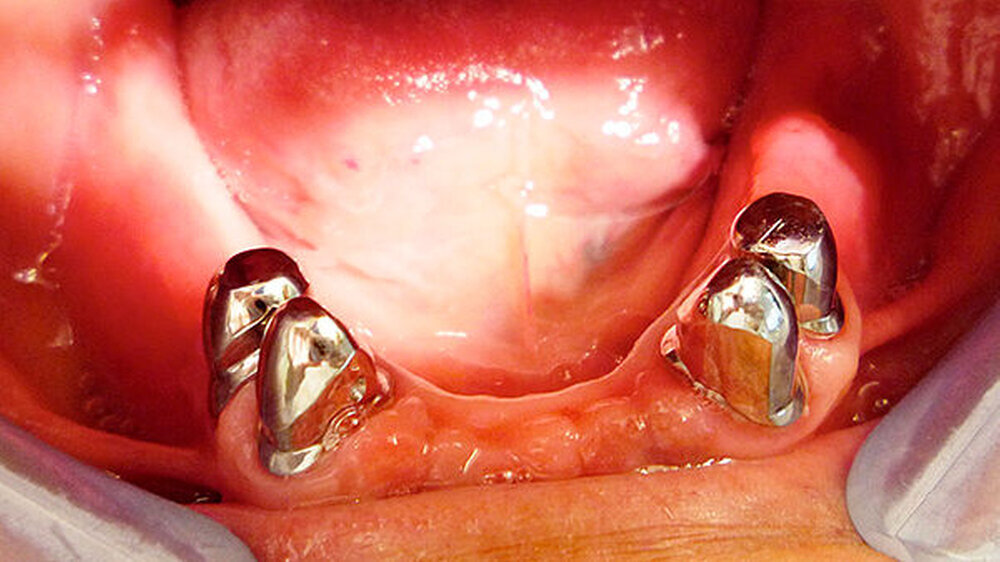

Die Abbildungen 4 bis 8 zeigen die Situation nach vier monatiger ZE-Tragezeit. Nach ausgiebiger Extraktionstherapie und parodontaler Behandlung der Restzähne wurde im Oberkiefer eine Cover-Denture-Totalprothese inseriert und im Unterkiefer eine parodontal abgestützte Teleskopprothese mit verblendeten Teleskopen 34,35,44,45.

Es sei dazu folgendes anzumerken, schreiben die Behandler: D"ie Einstellung des Patienten zu seiner Mundhygiene hat sich plötzlich grundlegend geändert. Die Prothese zeigt nach vier Monaten einen ausgezeichneten Pflegezustand, obwohl der Patient starker Raucher ist und vorher ja die bekannten parodontalen Probleme hatte. Alle Pfeilerzähne sind absolut fest und ohne Lockerung, obwohl sie vorher noch Lockerungsgrad I zeigten. Auch die Pfeilerteleskope sind sehr gut gepflegt. Der Patient hat seine Recalltermine nun zuverlässig wahrgenommen."